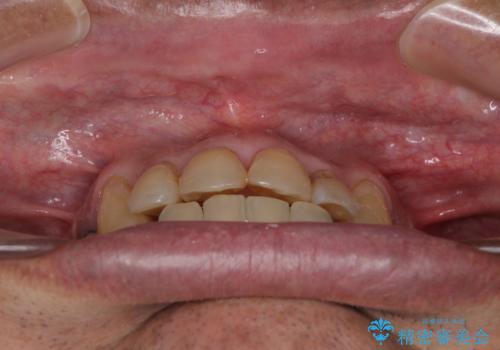

歯列不正と歯周病 総合歯科治療による全顎治療

全体的に中等度の歯周病と診断されたため、歯周外科処置やインプラントによる咬合回復から進めて行き、矯正治療による歯列改善を行った後にオールセラミッククラウンにて補綴することとしました。

歯槽骨の再生治療を行ったため、外科処置後の静置期間がながくなり、4年弱の治療期間となりました。

初診来院時には矯正治療を行うことは想像していなかったようで、治療後には咬みやすさだけでなく、前歯が大変審美的に仕上がり、患者様には大変満足していただきました。